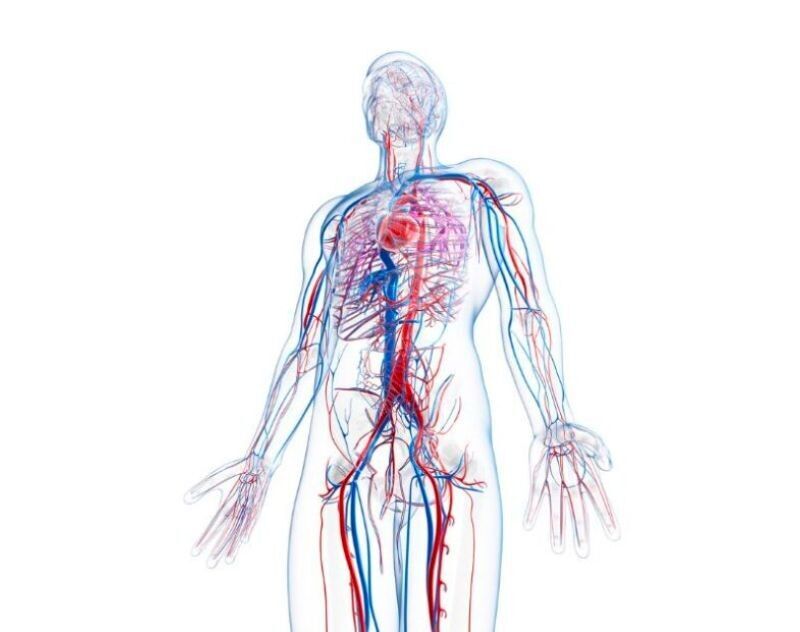

A vascular surgeon is a medical doctor who specializes in the diagnosis and treatment of disorders of the vascular system, which includes the arteries, veins, and lymphatic vessels. Vascular surgeons are trained to perform a variety of procedures, including open surgery, endovascular procedures (procedures performed inside blood vessels using a catheter), and minimally invasive procedures. They may also provide medical management for patients with vascular conditions, including prescribing medications and developing treatment plans. Vascular surgeons may treat a wide range of conditions, including arterial aneurysms, carotid artery disease, peripheral artery disease, and venous insufficiency. They may also perform surgery to repair or bypass blocked or damaged blood vessels.